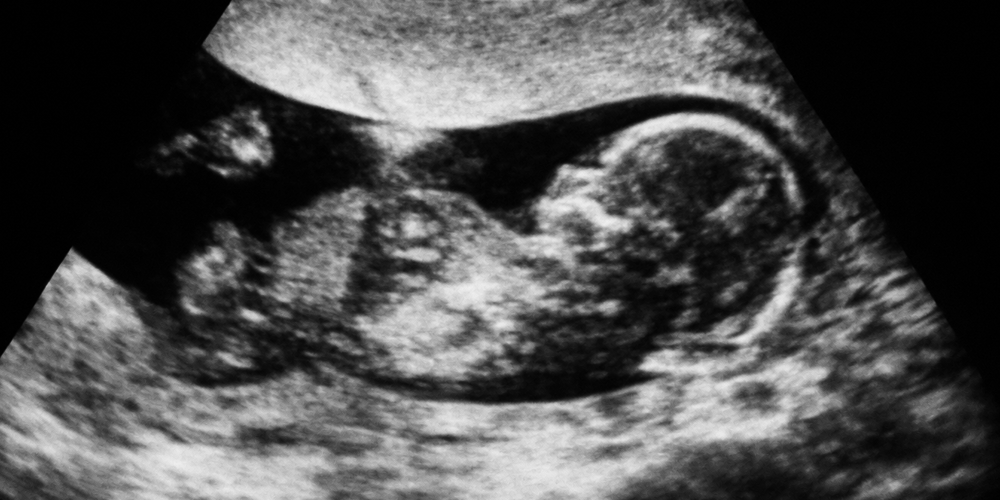

Amniyosentez ile ilgili de çok bilgi var internette. Benim katkım da aşağıdaki şekilde: